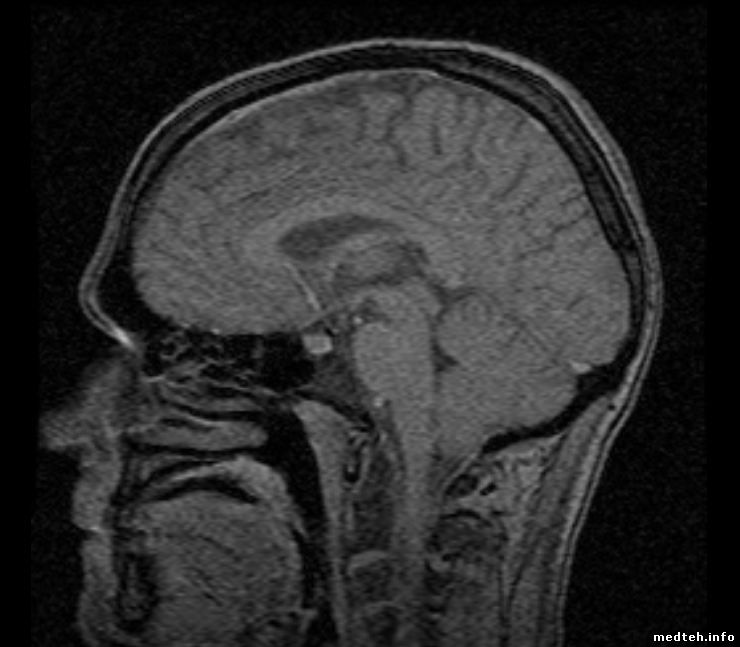

Вот что имеем:

Больше похоже на 0,3 Тесловый аппарат.

Результат SPT:

Noise от 39 до 59, в выходные 28

Signal от 1207 до 1350

Head gre stab - marginal

Shim - marginal (по отдельным тестам общая картина однородности поля в норме)

Body fse stab - marginal

Body gre stab - marginal

Coherent noise - marginal

Eddy Current Y и Z - marginal (будем править графиди, но в корне ситуацию это не поправит)

Ве остальное - pass

Тест иногда проходит на OK если в отделении выключить лампы в которых стоят китайские драйверы, иногда и это не помогает...

8319532.jpg (57.6 Kb) · 6484475.jpg (59.4 Kb) · 9377589.jpg (61.4 Kb) · 9481969.jpg (45.3 Kb)